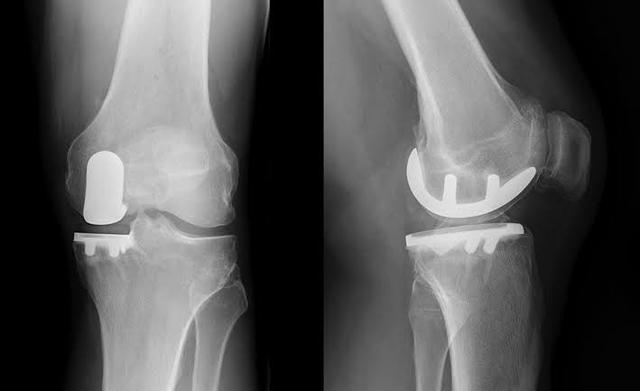

関節の症状が特に重く、患者さんが明らかな関節の変形普通に歩くことができず、500メートル以上歩くと関節に著しい痛みがあり、安静時や睡眠時の痛みがひどい場合は、人工関節置換術の適応となります。人工膝関節置換術が、患者を完全に救う唯一の方法かもしれない。。

9.人工膝関節置換術変形性膝関節症が明らかに関節の変形を引き起こし、患者の生活に深刻な影響を及ぼすようであれば、人工膝関節置換術によって患者の問題を完全に解決しなければなりません。

遅発性:激しい痛みを和らげるための人工関節

病気の後期になると、患者の軟骨はほとんどすり減ります。軟骨のクッションがなければ、骨と骨が直接こすれ合うことになる。この段階では、人工関節に置き換えるか、関節固定術を行うかしか選択肢はありませんが、術後の患者の運動能力に深刻な影響を及ぼす可能性があるため、ほとんど行われません。